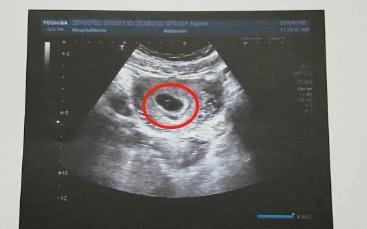

5、孕囊看男女

首先,早孕期孕囊里包裹的除了胚芽还有一些羊水。我们可以想象一下,兜着水的气球,放在桌子上会变成什么形状。

孕囊就是这种不规则的类椭圆体,也就是讲,孕囊是一个很容易变换形状非常Q弹的小肉球。

此外,孕期,不管是腹壁B超还是经阴道B超,都是无法做到三维重建,只能根据超声检测到的2-3个径线来描述孕囊的大小。

大家拿到手的B超报告,数值接近的,容易被理解为是圆形,有的数值差距太大,就被理解为椭圆形。

这个和男女半毛钱关系都没有,只是超声扫描到的切面不同测到的数值不同而已。

而且孕囊受到挤压是非常容易变化的的,比如比如你做B超的时候,尿多了也许它就扁了,尿不多也许它就圆了,你用B超探头压来压去,它就扁了又圆了又扁了又圆了。

所以,孕囊判断男女大家当做娱乐就好了,不要太当真。